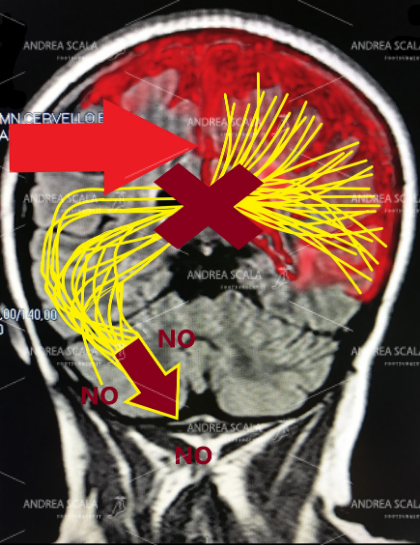

Lo schema mostra in modo elementare che dopo l’ictus le cellule cerebrali muoiono. Dopo l’emorragia (oppure l’ischemia) non avviene il passaggio degli impulsi elettrici dall’altra parte del cervello. Tutti sanno che la parte del corpo opposta all’ictus rimane paralizzata. Si verifica l’emiplegia. Il piede e la caviglia di deformano e non consentono l’appoggio al suolo.

I professionisti della Riabilitazione che curano gli esiti dell’ictus creano una confusione tra paralisi degli arti (emiplegia) e ripresa delle facoltà cerebrali. L’evoluzione della malattia del cervello non c’entra nulla con la paralisi del piede. Sono due cose distinte e separate. Il cervello riprende alcune facoltà dopo l’ictus perché interviene l’emisfero che non è stato toccato dall’ictus. Ma il cervello non potrà mai più mandare impulsi elettrici in periferia agli arti paralitici.

Le facoltà del cervello quali la parola, la memoria, i sentimenti, i ricordi ecc. ecc. riprendono grazie alla parte che non è stata toccata dall’ictus. Dopo la morte dei neuroni (le cellule cerebrali) non c’è rigenerazione verso la periferia. Gli ordini per il movimento degli arti non partono perché non c’è la elettricità. I neuroni che sono nel midollo spinale rimangono privi di ordini superiori. I muscoli degli arti ricevono ordini disordinati e non regolati dal midollo spinale. Per questo motivo alcuni muscoli sono immobili e paralitici e altri sono ipertonici e spastici. Per questo motivo il movimento è inconsulto e disordinato.